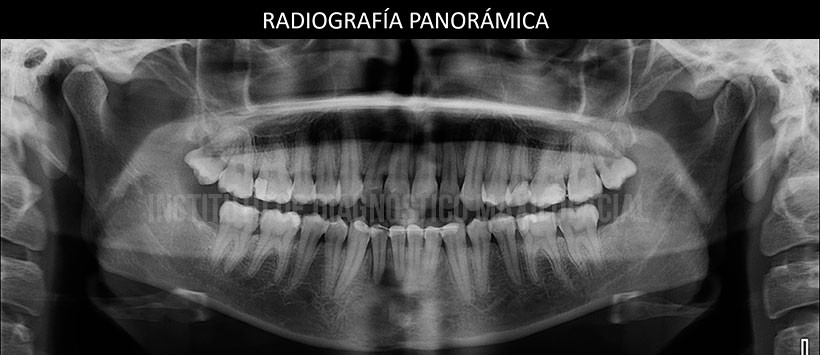

En la evaluación mediante la radiografía panorámica se observa un leve aplanamiento del contorno de ambos cóndilos mandibulares, alambre de contención en sector anteroinferior y ausencia de las piezas 38 y 48. Siendo lo mas resaltante una imagen radiolúcida de limites difusos en sínfisis mandibular, próxima a los ápices dentarios a predominio de las piezas 41 y 42. (Figura 2)